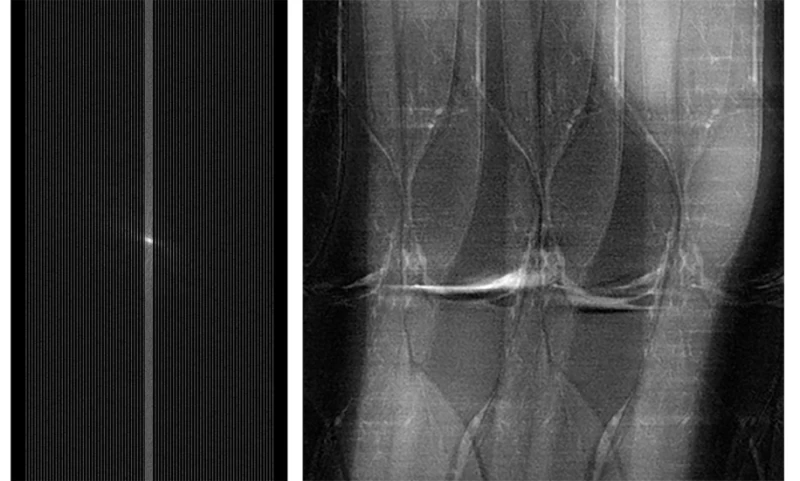

AIをこのように使うことのメリットは、人体の内部を医師に見せる画像を作成する際に、従来の手法(逆フーリエ変換と呼ばれる)よりもはるかに少ない情報量で済むことだ。「MRIでは、一定量のデータを集めて再構成法を使って画像を作成します」とニューヨーク大学ランゴーン・ヘルスの放射線科長マイケル・レヒト氏は言う。「しかし、これまでおそらく必要以上のデータを集めてきたことが判明しました」。燃費の良い車がガソリンを大量に消費するガタガタ車に取って代わるようなものだと考えてみよう。新しいアルゴリズムでは、MRI装置と同じ距離(この場合は正しい画像を取得する)を進むのに、より少ない測定から得られるデータしか必要としない。

しかし、このように実績のある機械が生成する情報をアルゴリズムに解釈させるのは容易なことではありません。AIソフトウェアが周波数データを正しく画像に変換できるように訓練するため、Facebookチームは実際のMRIスキャン情報を用いて約1,000種類の異なるモデルを試したと述べています。アルゴリズムに生の情報を与えるだけでなく、対応する画像も提示することで、ニューラルネットワーク(写真に写っているものを認識するなど、ソフトウェアエンジニアが様々なタスクを訓練できる一般的な機械学習ツール)が正しい画像を生成できるようにしました。

Facebookは、AI-MRIアルゴリズムを一般公開すると発表しました。これにより、機械の高速化や人工知能を用いたデータ解釈による画像化といった目標に取り組みたい他の研究者も、その目標に取り組めるようになるためです。「MRIスキャナーは高価で、頻繁にバックアップされるため、臨床現場でのAI導入の影響は甚大です」とマズロウスキー氏は述べています。しかし、AIをプロセスに組み込むことには潜在的なリスクがいくつか存在します。例えば、アルゴリズムによって実際には存在しない問題(アーティファクト)が作り出される可能性があります。さらに重要なのは、マズロウスキー氏によると、実際の問題を見落とし、放射線科医が前十字靭帯断裂に気付かない可能性があることです。

これは非常にリスクの高いプロジェクトであり、非常に重要な見返りが期待できます。外科医はスキャンの結果に応じて、切開するかしないかを決める可能性があります。「本当に不安です」とジトニック氏は言います。「これらのことを正しく行うことが重要です。だからこそ、私たちは非常に計画的に作業を進めているのです。」

互換性研究が学術的な審査を待つ間、ニューヨーク大学の研究者たちは、AIが生成した画像が、外科医が膝関節鏡検査を行う際に実際に目にする画像と一致するかどうかを評価するための更なる比較研究の準備を進めています。将来の目標は、この技術を膝関節だけでなく、現在非常に長いスキャン時間を必要とする脳MRIなど、他の部位にも適用することです。